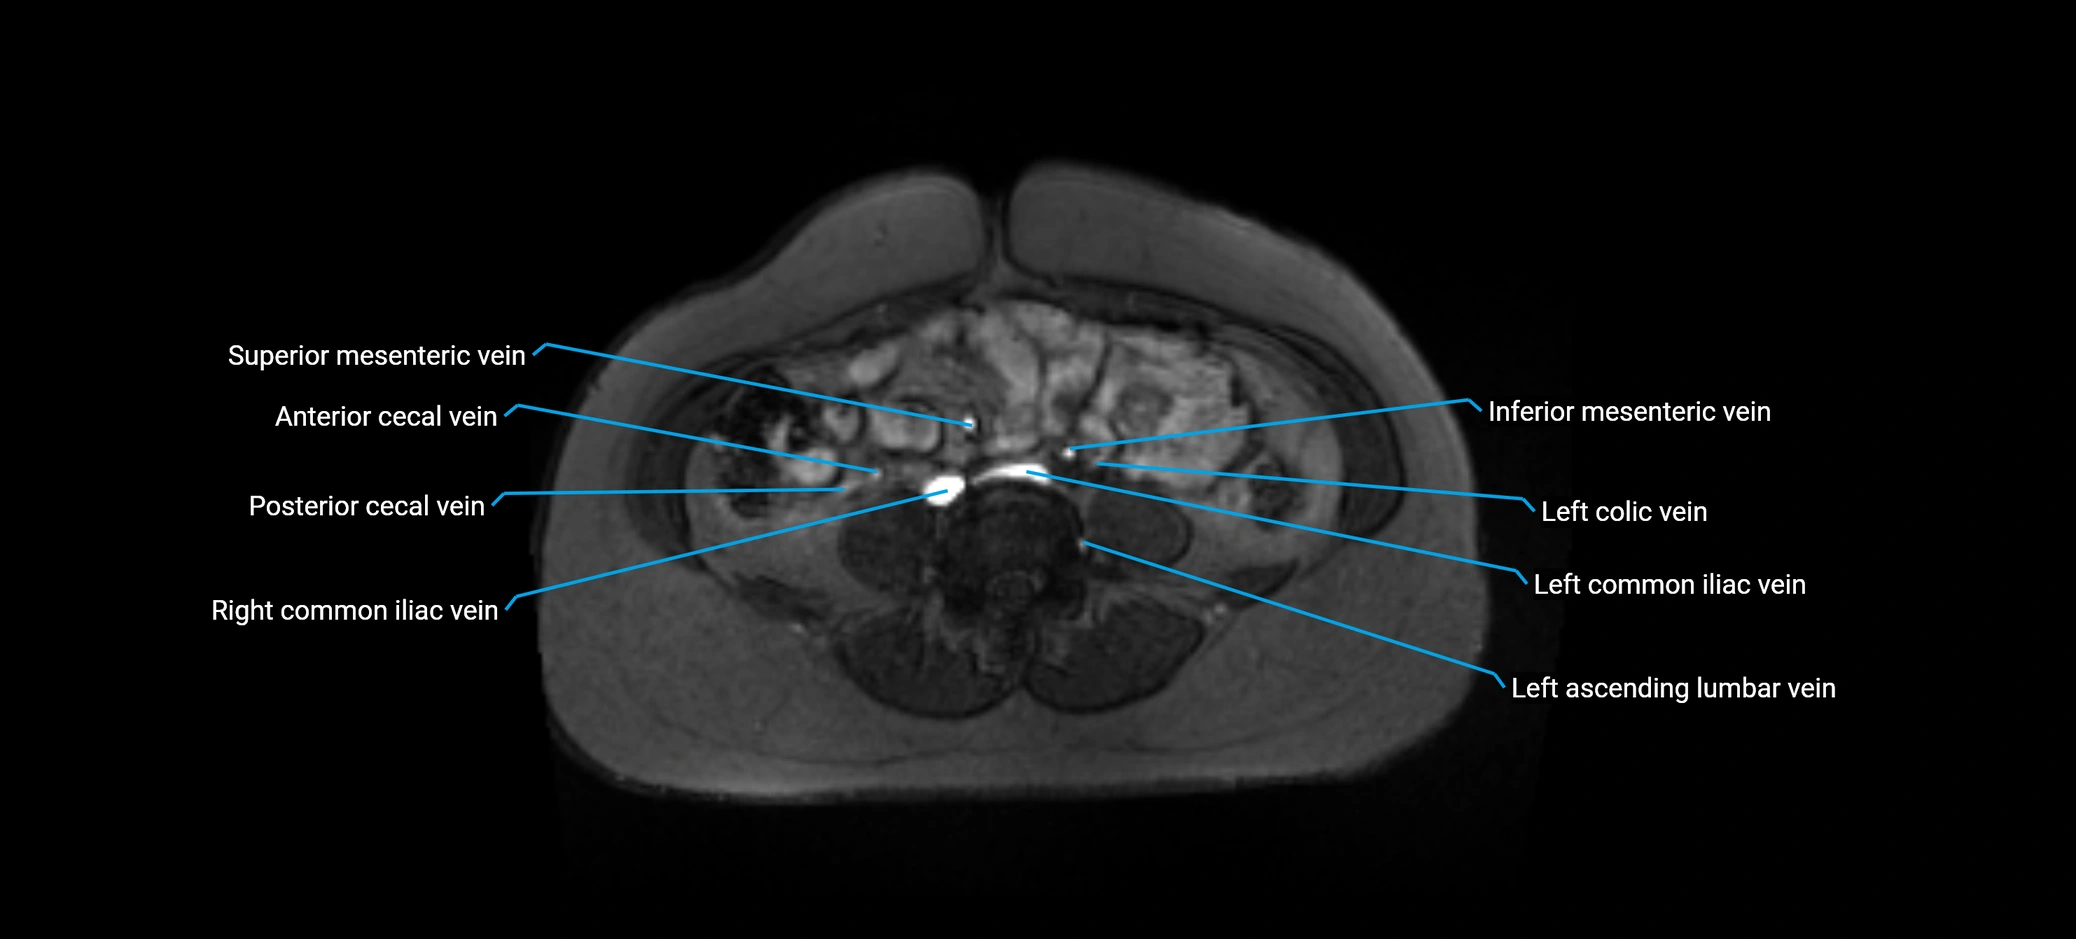

MRI image

image